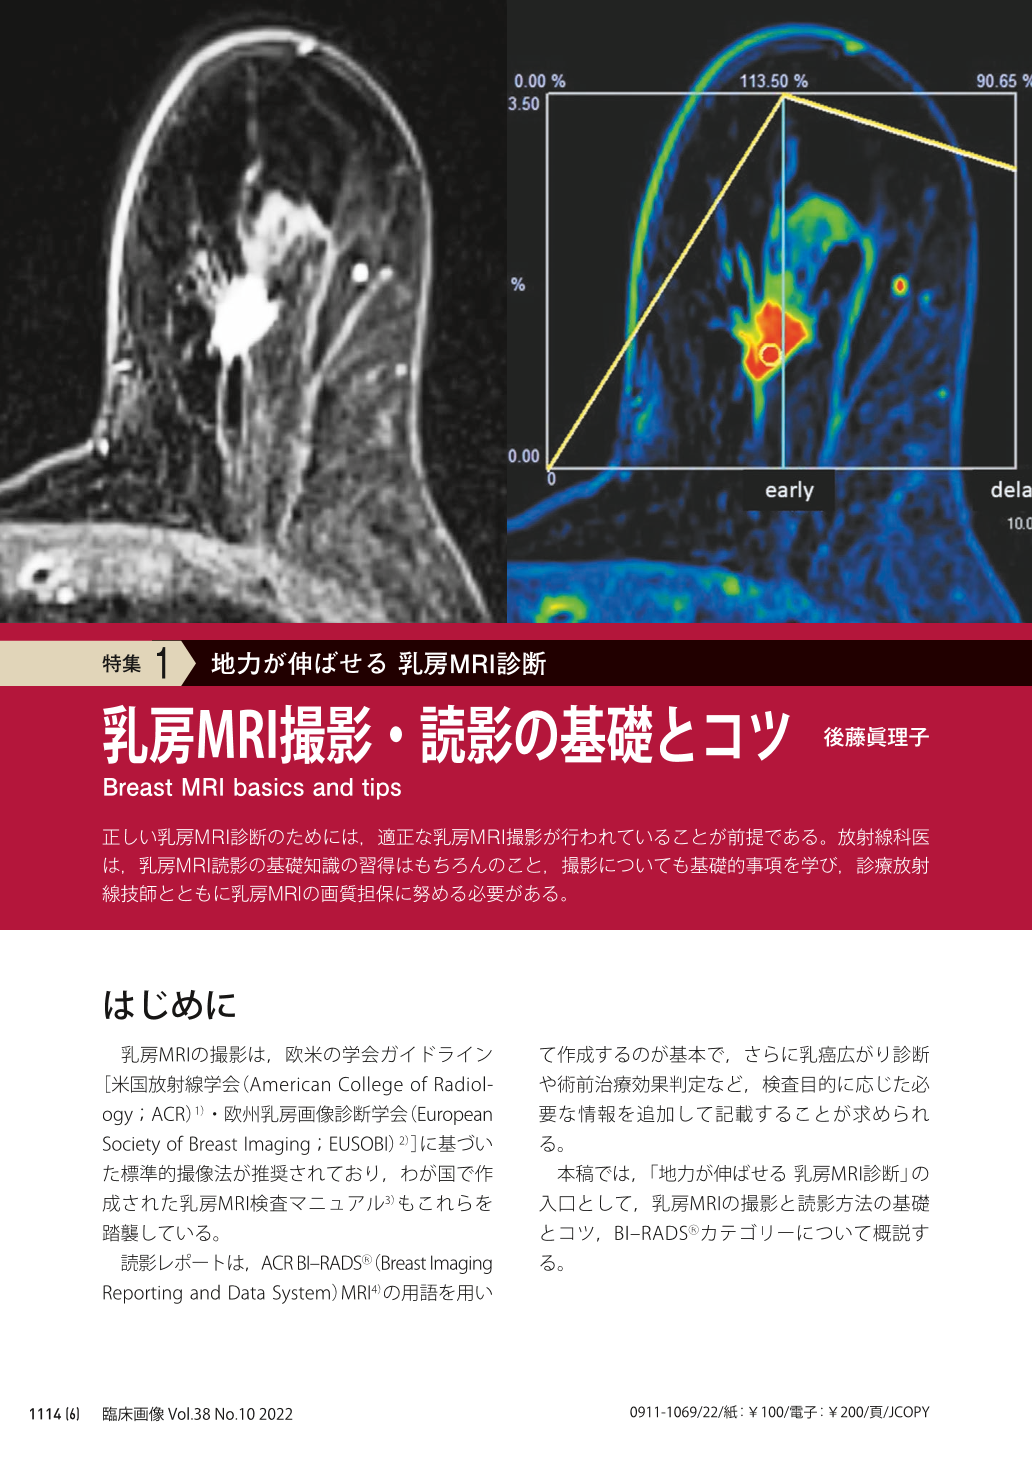

乳房MRIアトラス | 五味 直哉, 菊池 真理, 五味 直哉, 菊池 真理。乳房MRIアトラス 裁断済 書き込みなし 乳腺MRI。乳房MRIアトラス 裁断済 書き込みなし 乳腺MRI 本。人気アルファ米5種セット 25袋。婦人科MRIアトラス 改訂第2版 (画像診断 別冊KEYBOOKシリーズ。乳房MRI撮影・読影の基礎とコツ (臨床画像 38巻10号) | 医書.jp。乳房MRI | 那珂川市の病院ならCT・MRI検査が可能な吉田。ご覧いただきありがとうございます!専用の機械で裁断してありますが、素人裁断のものです。1ページずつバラバラになってます。裁断済みである事がご理解いただける方のみ購入してください。『裁断済み』のため状態を『傷や汚れあり』にしていま「乳房MRIアトラス」五味 直哉 / 菊池 真理 / 菊池 真理定価: ¥ 9200#五味直哉 #五味_直哉 #菊池真理 #菊池_真理 #菊池真理 #菊池_真理 #本 #自然/医療・薬学・健康。MRI-乳腺MRIの質と安全性を向上させるSmartExam Breast-技術。乳房MRI検査 獨協医科大学埼玉医療センター 放射線部。乳房MRI造影以外のシーケンスの活用法 (臨床画像 38巻10号。乳房MRIアトラス | 五味 直哉, 菊池 真理, 五味 直哉, 菊池 真理。BI-RADSを克服する・Mass編【造影乳房MRIを読めるようになる。乳腺MRI検査・検診 – AIC八重洲クリニック 乳腺外科